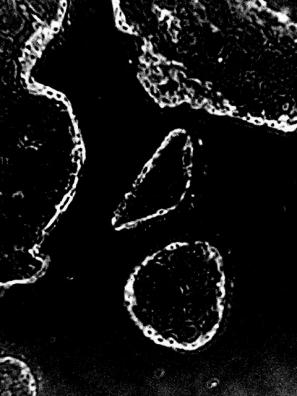

При

строкових пологах (37-40 тижнів гестації) інтенсивність світіння цитоплазми

трофобласта хоріальних ворсин після обробки люмінолом було вищим, ніж у

попередні терміни вагітності. У групі контролю середня інтенсивність світіння була

оцінено у 184,1±4,27. Однак, це світіння набувало рис вираженого фракціонування

по площі цитоплазми (3а). При ЗДАВ світіння було оцінено в 204±5,71, а

фракціонування по площі цитоплазми, такого, як у групі контролю не відмічалося.

Різниця між групами дослідження за критерієм Mann-Whitney

була вірогідною (p<0,001).

Рис.3. Світіння цитоплазми трофобласта хоріальних ворсинок після

обробки люмінолом при довжині хвилі 425 нм. А) контрольна група. 39 тижнів

вагітності. Б) залізодефіцитна анемія. 39 тижнів вагітності. Мікроскоп ЛЮМАМ-8.

Об.20х. Ок.10х.